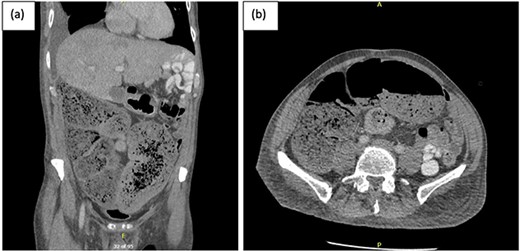

The colorectal team was consulted, and the patient received increased doses of aperients and suppositories as well as regular abdominal X-ray screening to monitor for colon dilatation. Despite this, the patient had minimal clinical improvement with ongoing abdominal bloating and pain and lack of bowel action, presenting a clinical dilemma of pseudo-obstruction, or AL with colonic involvement. A decision was made to proceed with flexible sigmoidoscopy, which found distended colon with faeces in the lumen, no mucosal changes to suggest ischaemia, and no obvious mechanical obstruction (Fig. 2).

Flexible sigmoidoscopy demonstrating distended (a) transverse and (b) descending colon with faeces in the lumen and no mucosal changes to suggest ischaemia or inflammation.